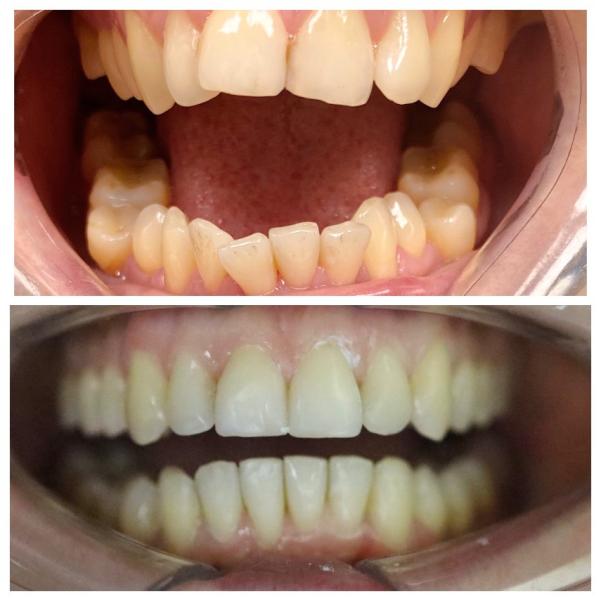

Как я исправила прикус за 2 года? История с элайнерами

Делюсь сложным кейсом лечения на элайнерах длиной в 2 года и 1 месяц.

Потребовалось удаление всех восьмерок и терпение пациента к улыбке своей мечты. Мы очень довольны результатом.

Отличный результат! Прикус полностью изменился..